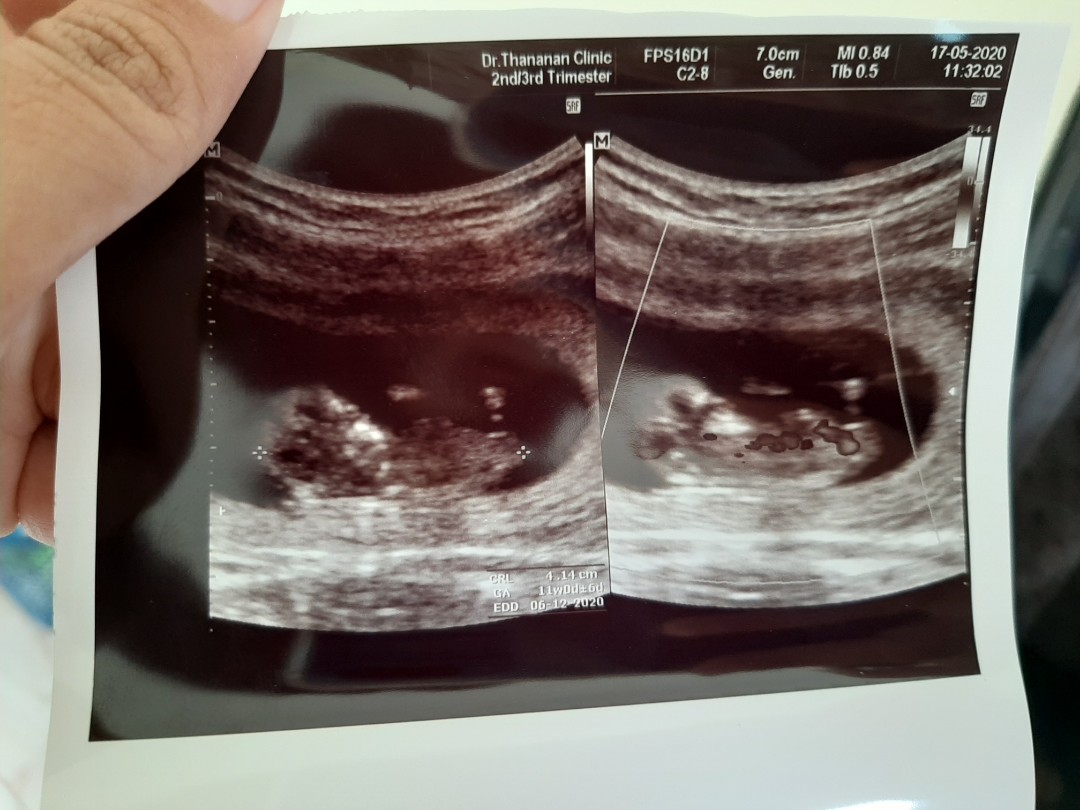

ขอดูใบซาวหน่อยจ้า เเล้วกำหนดคลอดวันที่เท่าไรกันค่ะ

12 ธันวาคมค่ะ